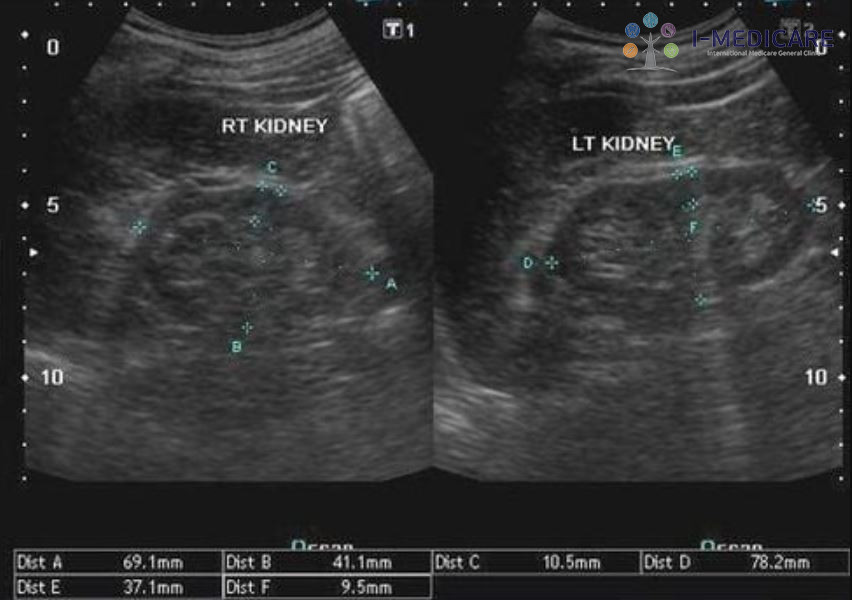

Siêu âm giúp đánh giá chính xác kích thước và cấu trúc tuyến giáp, cung cấp thông tin quan trọng cho việc chẩn đoán và theo dõi điều trị.

- Đo kích thước và thể tích tuyến giáp: Bác sĩ có thể xác định kích thước từng thùy và eo tuyến, tính toán thể tích toàn tuyến. Giá trị bình thường khoảng 10-15 ml ở nữ và 12-18 ml ở nam.

- Theo dõi bướu giáp và hiệu quả điều trị: Thể tích tuyến giáp là thông số quan trọng để theo dõi sự phát triển của bướu hoặc đánh giá đáp ứng sau điều trị.

- Đánh giá cấu trúc mô tuyến: Tuyến giáp khỏe mạnh có cấu trúc đồng nhất, độ phản âm cao hơn cơ. Nếu thấy vùng giảm âm, không đồng nhất hoặc xuất hiện nhiều nốt nhỏ, đó là dấu hiệu bất thường cần được kiểm tra thêm.